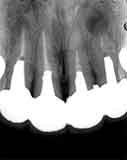

残念ながら左上の2番(|2)には根尖病巣があります。しかもかなりの金属ポストが 装着されていますのでちょっと厄介そうです。審美的に問題がないこと、今のところ症状もない ようですのでこのまま使用していただいて、何か症状がでた段階で、除去→根管治療を行い ます。

2-|-2は同時期に治療されたということですのが右上の2本に関しては問題ありませ ん。問題の左上も進行が非常に緩慢で、根管治療自体は丁寧にされていたようです。根管治療 は全て成功するとは限りませんので、この程度なら“仕方がない”の範疇です。

犬歯にはムシ歯もありましたが、“滲み”の原因はムシ歯ではなく歯肉の炎症が原因と思われま す。